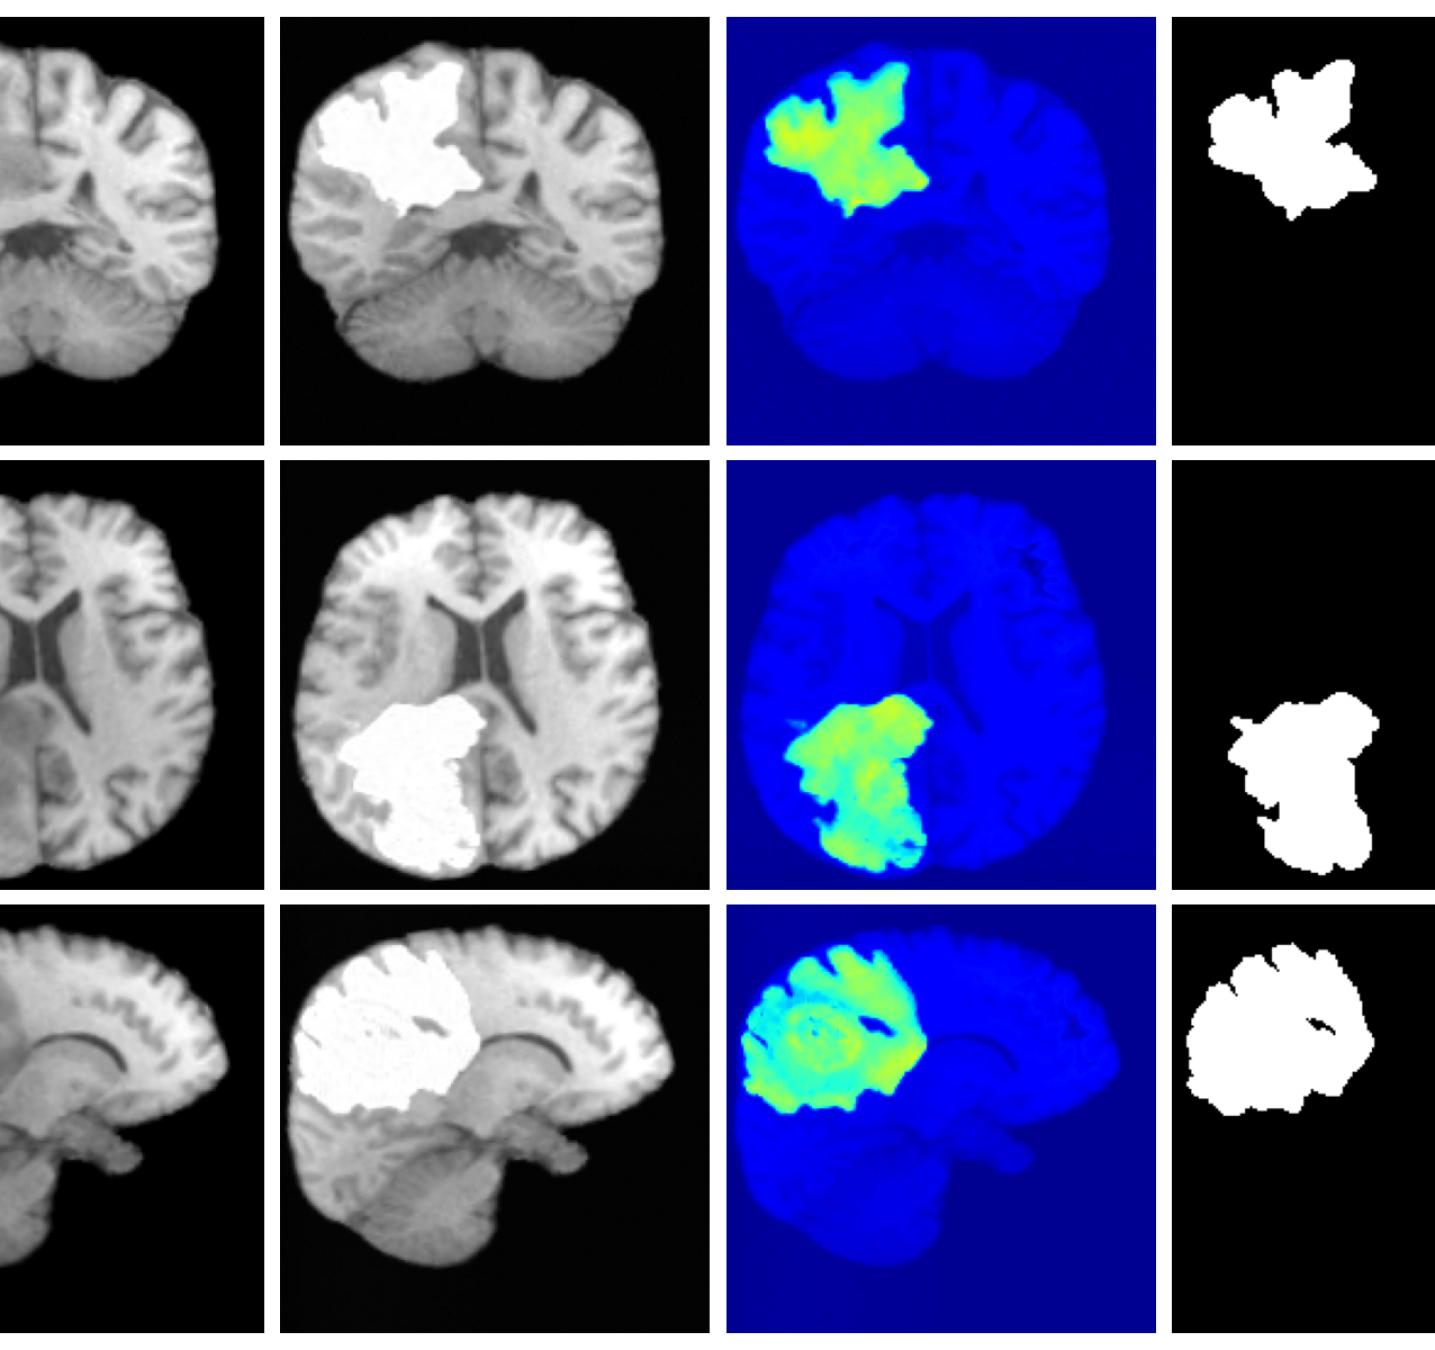

4.3 Image inpainting results

Inpainting results are given in Table 2. Our method achieves the best overall performance, attaining the highest rank on both datasets. For ATLAS, our method outperforms all baselines with improvements of 39.2% (VAE), 8.3% (VAE), 2.7% (VAE), 44.2% (LDM), 19.0% (LDM), and 51.4% (LDM). On BraTS, it improves over the best baselines by 25.6% (VAE), 5.2% (VAE), 27.4% (LDM), and 15.2% (LDM), while remaining competitive on the remaining metrics.

Figure 3 (additional examples in Appendix A.9) shows that SynthSR preserves healthy tissue but struggles with large lesions, while DDPM-2D and DDPM-3D, despite producing high-contrast anomaly maps, generate unrealistic homogeneous inpainting, consistent with their lower performance in Table 2. In contrast, our method yields the most anatomically plausible inpainted regions, although anomaly maps appear subtle due to low contrast between lesions and healthy tissue.

A.9 Additional qualitative inpainting results

Additional qualitative results for the ATLAS and BraTS datasets are given in Figures 12 and 13, respectively.